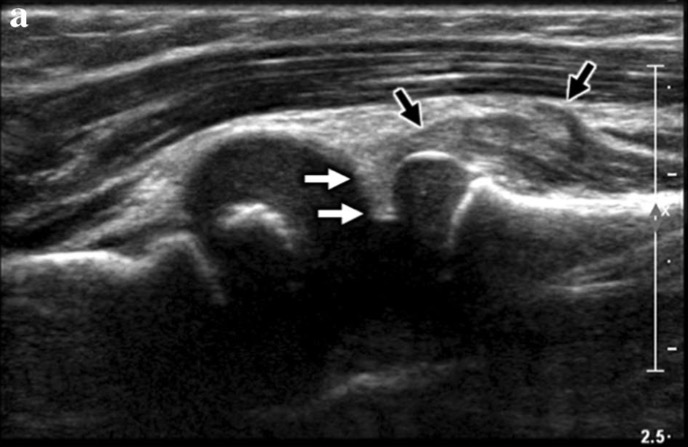

A. US longitudinale à travers l'articulation radiocapitellaire montre:

- ligament annulaire échogène interposé entre l'articulation radiocapitellaire (flèches blanches)

- muscle supinateur élargi et hétérogène (flèche noire) qui est positionné proximalement

La combinaison de ces résultats a été décrite comme un « signe J » ou un « signe crochet »